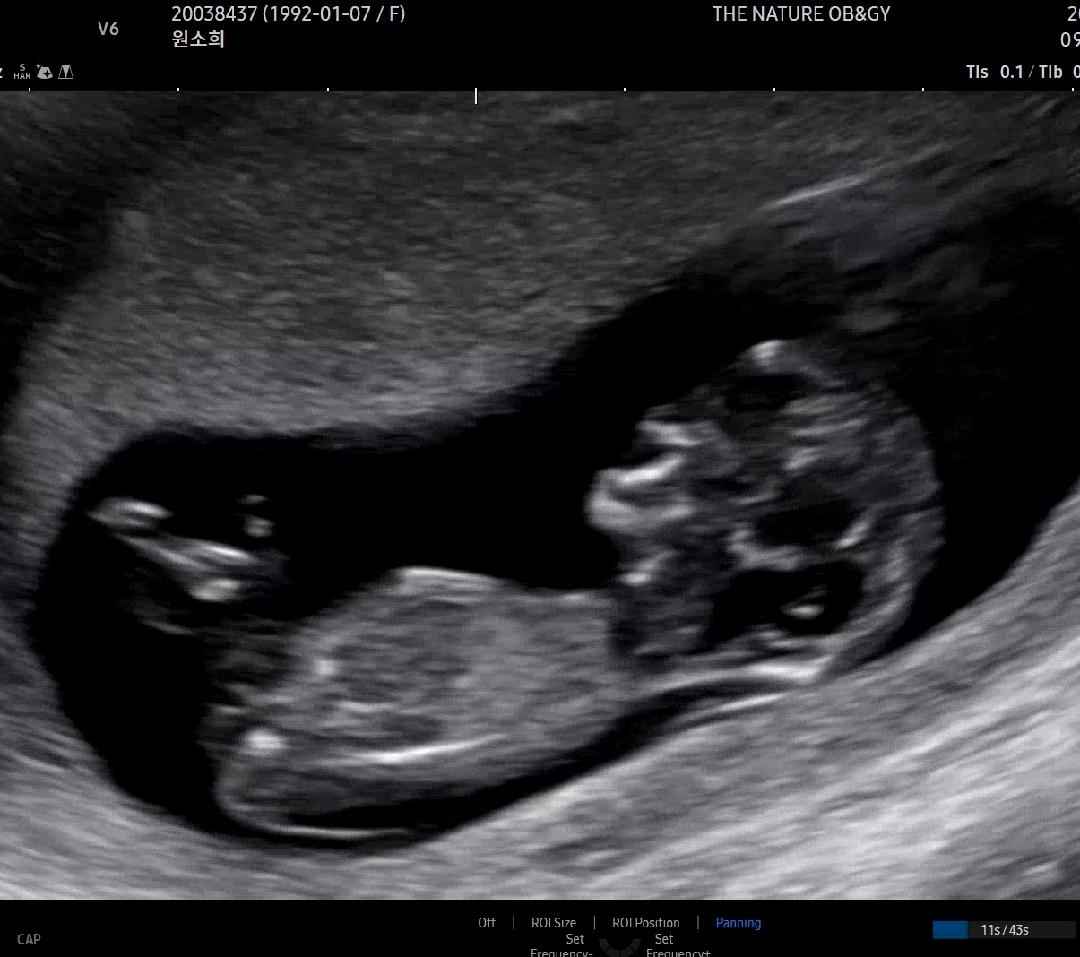

각도법 참견부탁드립니당👶🏻🙏🏻

오늘 1차 기형아 검사 받고 왔어요!!! 딸일까요??? 아들일까요??? 참견부탁드립니당😊